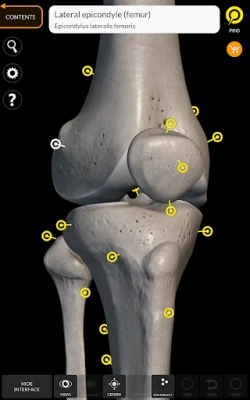

"Skeleton | 3D Atlas of Anatomy" is a next generation anatomy atlas in 3D which gives you availability of interactive highly detailed anatomical models!

Each bone of the human skeleton has been reconstructed in 3D, you can rotate and zoom in on each model and observe it in detail from any angle.

By selecting models or pins you will be shown the terms related to any specific anatomical part, you can select from 12 languages and show the terms in two languages simultaneously.

HIGHLY DETAILED ANATOMICAL 3D MODELS

• Skeletal System

• Accurate 3D modeling

• Surfaces of the skeleton with high resolution textures up to 4K

• Rotate and Zoom every model in the 3D space

• Division by regions for a clear and immediate visual of each structure

• Interactive Pin allow visualization of the term relative to every anatomical detail